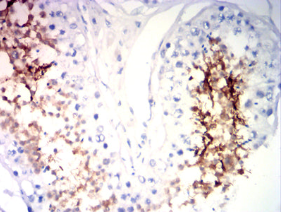

IHC    1/200-1/1000